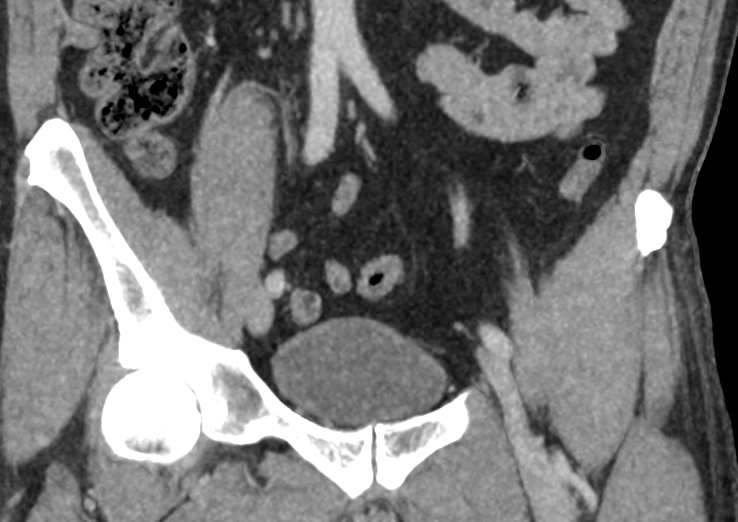

В брюшной полости и забрюшинном пространстве расположены группы лимфатических узлов, которые окружают внутренние органы (желудочные, печеночные, брыжеечные, чревные, подвздошные и др) и располагаются вдоль крупных кровеносных сосудов. Лимфоузлы относятся к периферическим органам иммунной системы человека и выполняют защитную функцию, являясь барьером для проникновения инфекций и задерживают распространение раковых клеток.

Патологические изменения регионарных лимфоузлов часто свидетельствуют о поражении того органа, от которого происходит лимфоотток. Это имеет важное значение для оценки распространенности онкологического процесса, выявления отдаленного метастатического поражения лимфатической системы, а также используется для определения тактики лечения. Кроме того, патология лимфатических узлов может говорить о развитии гемобластозов и лимфопролиферативных заболеваний крови.

Компьютерная томография позволяет детально визуализировать структуру лимфатических узлов, выявить ее неоднородность, гиперплазию, определить деформацию контуров, появление инфильтрации окружающих тканей с образованием пакетов и конгломератов лимфоузлов.